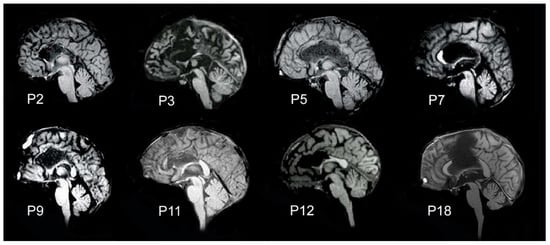

| Patient | Gender | Age | I.Q. | Oldfield Score | Callosal Resection | Years from Surgery | DTI | Stimulus Side | Stimulation Protocol |

|---|---|---|---|---|---|---|---|---|---|

| P2 | M | 51 | 81 | 10 (right) | total | 21 | yes | L, R | p2 |

| P3 | M | 30 | 83 | 21 (right) | total | 11 | yes | L, R | p2 |

| P5 | F | 27 | 70 | 10 (right) | total | 10 | yes | L, R | p1 |

| P7 | M | 48 | 88 | 10 (right) | partial posterior | 7 | yes | L, R | p2 |

| P9 | M | 35 | 70 | 46 (left) | partial anterior | 16 | yes | L, R | p1 |

| P11 | M | 36 | 70 | 10 (right) | partial anterior | 15 | yes | L, R | p2 |

| P12 | F | 32 | 70 | 12 (right) | partial anterior | 17 | yes | L, R | p2 |

| P18 | M | 26 | na | 10 (right) | partial central | 2 | yes | R | p2 |